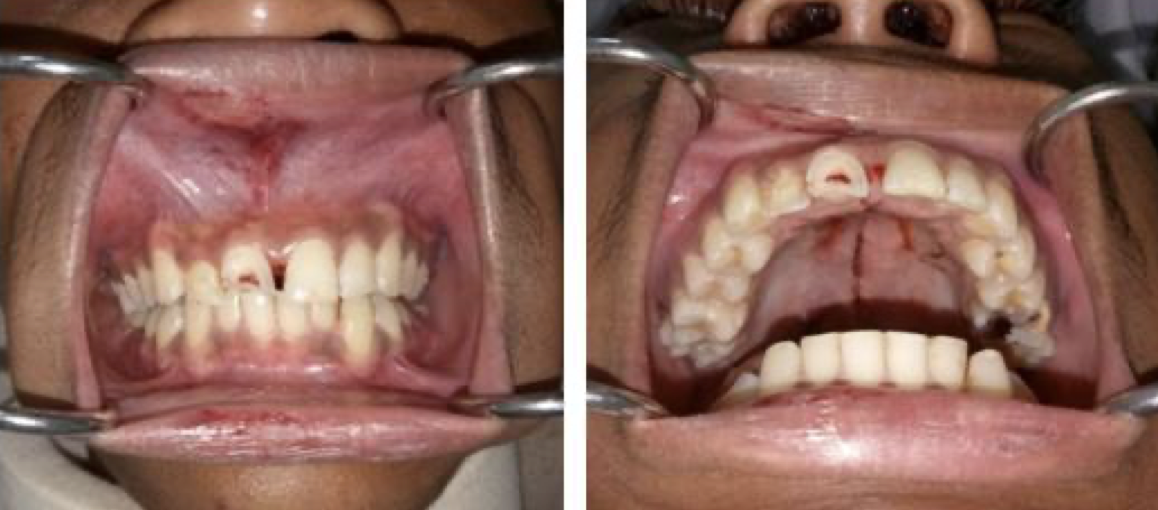

How is the anatomy different in cleft palate?

What is a submucous cleft, what is the incidence?